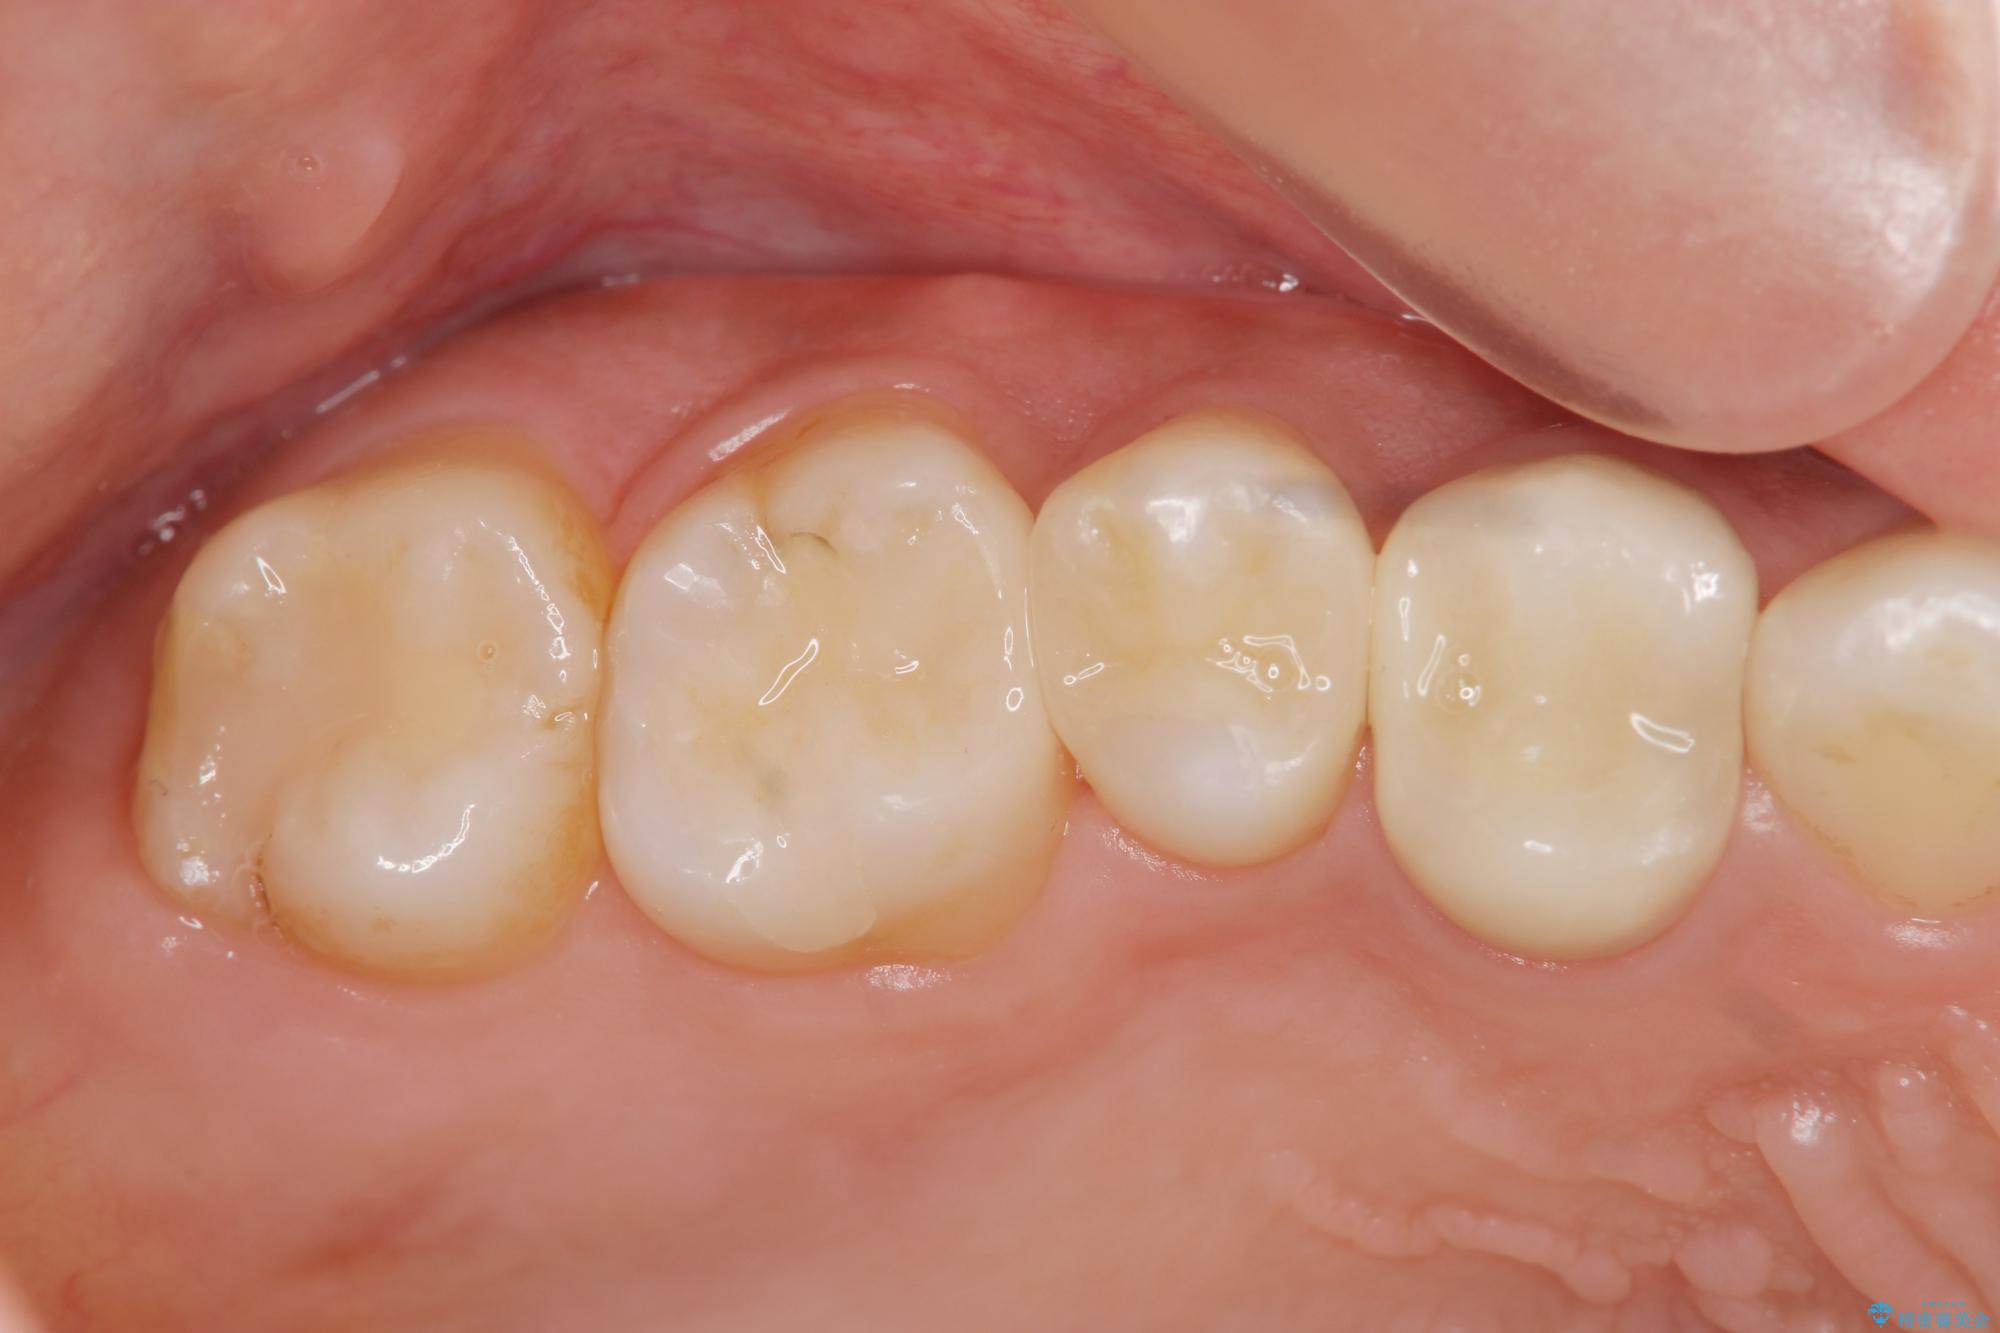

治療後

銀歯を除去してのセラミック治療[ メタルフリー ] 治療後画像 銀歯を除去してのセラミック治療[ メタルフリー ] 治療後画像 銀歯を除去してのセラミック治療[ メタルフリー ] 治療後画像

治療を終えて

セラミックインレーは審美性に優れるだけでなく、表面の物性が劣化しにくいこと、適合に優れることで虫歯の再発リスクが銀歯よりも優位に低くなります。